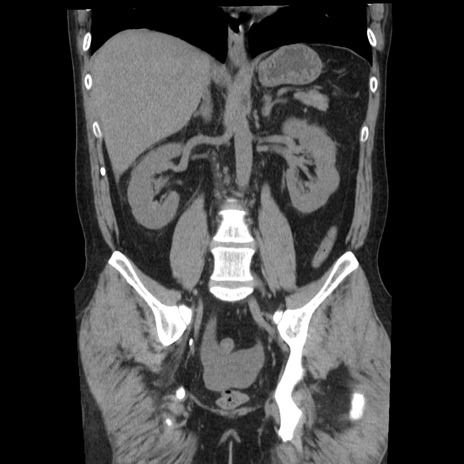

症例29(冠状断像)

【症例】40歳代男性

【現病歴】2日前から胃痛あり。徐々に周期的な激痛に変化した。本日になっても激痛があるため受診。

【身体所見】意識清明、BT 38-39℃台あり、腹部:膨満、やや硬、右下腹部に圧痛あり。

【データ】WBC 8500、CRP 23.26